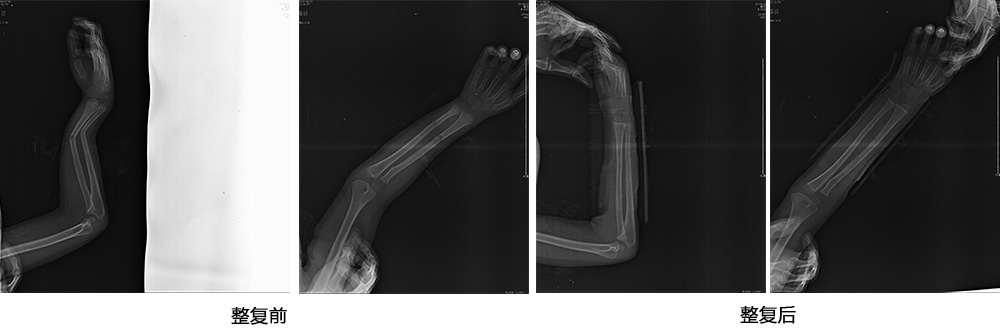

傳統(tǒng)手法整復病例影像

CR94676